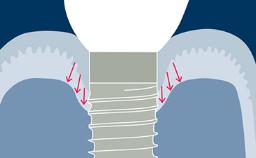

A terapia com implantes provou ser uma modalidade de tratamento bem-sucedida, aplicável em uma ampla gama de indicações clínicas para substituição dentária. Mesmo assim, as complicações ocorrem, e há evidências claras de que as complicações protéticas ocorrem em maior proporção com implantes dentários do que com dentes naturais. Geralmente chamados de “complicações estruturais”, é importante entender porque elas ocorrem e qual a melhor forma de lidar com elas. Este módulo classificará as complicações estruturais do implante associadas às próteses fixas como base para elucidar suas várias causas, melhor prevenção e manejo.